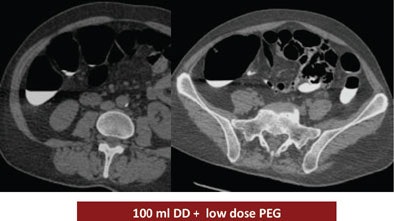

The study looked at three groups of 30 patients who underwent virtual colonoscopy after a same-day bowel preparation. Group 1 ingested 200 mL of undiluted DD the day of the exam, group 2 drank 100 mL of the agent the day of the exam, and group 3 ingested a low-dose polyethylene glycol (PEG) formula (macrogol) the two days before the exam, followed by 100 mL of DD the day of the exam.

| Above, the use of 200 mL DD in group 1 yielded the highest quality scores. While the colonic mucosa was well marked, significant volumes of fluid remained in the colon, similar to the 100 mL DD preparation (group 2, below). The use of 100 mL combined with low-dose polyethylene glycol over two days (bottom image) may have improved fecal tagging by softening the stool before the ingestion of DD. |